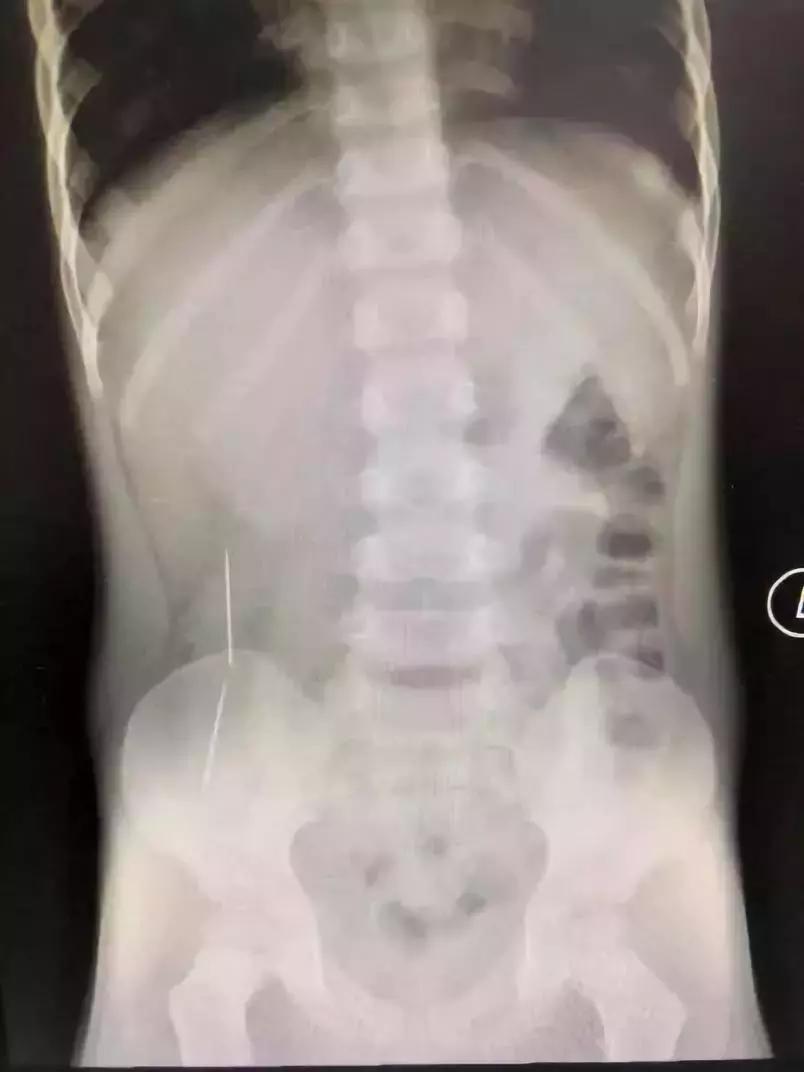

当时,看到X光片,在场所有的人都倒吸一口凉气。而且这两条已在彬彬肠胃穿游数日的绣花针,已穿透了他的肠管造成穿孔,他的腹腔内已造成了感染。情况十分不妙。